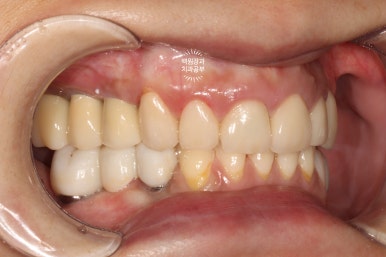

양 옆모습을 돌려서 보시면 위어금니와 아래어금니가 확연히 비교되는 것을 보실 수 있을겁니다.

일단 치아 경계 잇몸에 은색으로 보이는 부분 없이 깔끔하게 마무리가 되었습니다.

색상도 무조건 하얗지만은 않아서 개인적으로 더 자연스러워졌다고 봅니다.